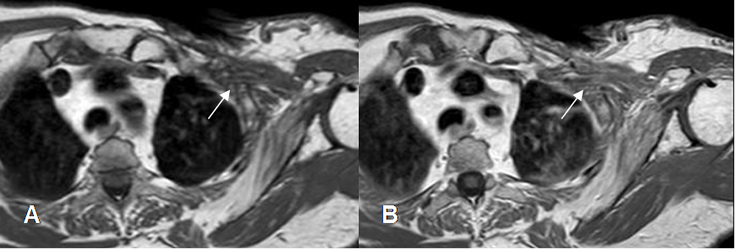

En todos los tumores malignos se encuentran lesiones hipointensas en T1 e hiperintensas en T2, que realzan con el contraste. Estos procesos producen efecto de masa o infiltran las raíces. (2). (Fig 14 y 15).

Fig 11. Neoplasia de pulmón.

A: TAC reconstrucción coronal, B: TAC axial en ventana de tejido y C en ventana ósea. Tumor pulmonar con extensión al espacio interescalénico. (Flechas delgadas). Hay destrucción ósea en la apófisis transversa vertebral y el origen de la costilla. (Flechas gruesas).